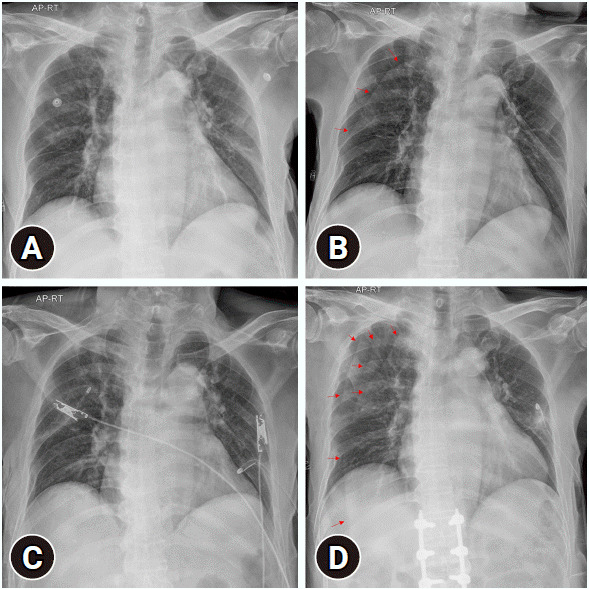

误解放射检查结果可能导致不必要的干预和潜在的患者伤害。在危急情况下,应对健康受损的创伤患者所需的紧迫性可能会增加误读胸部 X 光片的可能性。我们介绍了一名创伤患者的病例报告,该患者在复查胸部 X 光片时将皮肤褶皱伪影误认为是气胸,结果导致不必要的胸管插入。我们希望通过考虑位置、形状、锐利度和血管标记等因素,帮助其他人区分外伤患者胸部 X 光片上的皮肤皱褶和气胸。

Misinterpreting radiographic findings can lead to unnecessary interventions and potential patient harm. The urgency required when responding to the compromised health of trauma patients can increase the likelihood of misinterpreting chest x-rays in critical situations. We present the case report of a trauma patient whose skin fold artifacts were mistaken for pneumothorax on a follow-up chest x-ray, resulting in unnecessary chest tube insertion. We hope to help others differentiate between skin folds and pneumothorax on the chest x-rays of trauma patients by considering factors such as location, shape, sharpness, and vascular markings.